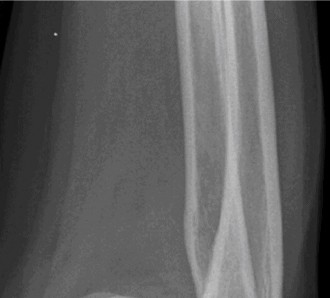

Understand common complications associated with performing surgery for scapulothoracic bursitis? CASE 33 A 42-year-old female presents to the office for follow up after sustaining a minimally displaced radial head fracture 3 months prior. She states she was initially treated in long-arm splint by the ER and did not follow up with an orthopaedic surgeon until now. Per her report, she removed the splint 4 weeks after the injury, but did not move her elbow due to pain. She now has no pain but is unable to reach that hand to her face or head. The remaining history is significant for previous ulnar nerve surgery for which she is unable to provide details. On physical examination, her upper extremity is normal except for limited flexion/extension, measured to be 80 to 50 degrees by goniometer. In addition, she has a well-healed surgical incision about the medial elbow, consistent with a previous surgery on her ulnar nerve. Her images are shown (Figs. 2–82 to 2–84).

Figure 2–82

Figure 2–83

Figure 2–84

What is the diagnosis?

- Early post-traumatic intrinsic joint contracture

- Late post-traumatic extrinsic joint contracture

- Late combined post-traumatic joint contracture

- Early combined post-traumatic joint contracture

Discussion

The correct answer is (A). Classification of post-traumatic elbow stiffness allows for better understanding of the disease and allows the clinician to treat the underlying cause of the joint contracture. Intrinsic causes include: any problem within the joint such as incongruency, loose bodies, or severe osteoarthritis. Extrinsic causes include capsular tightness, muscle contracture, heterotopic ossification, and skin contractures. Early is defined as within 6 months of the injury while late is considered to be greater than 6 months after the injury. Patients that present in the early time frame have a significantly better chance at having a good result both from nonoperative and operative treatment.